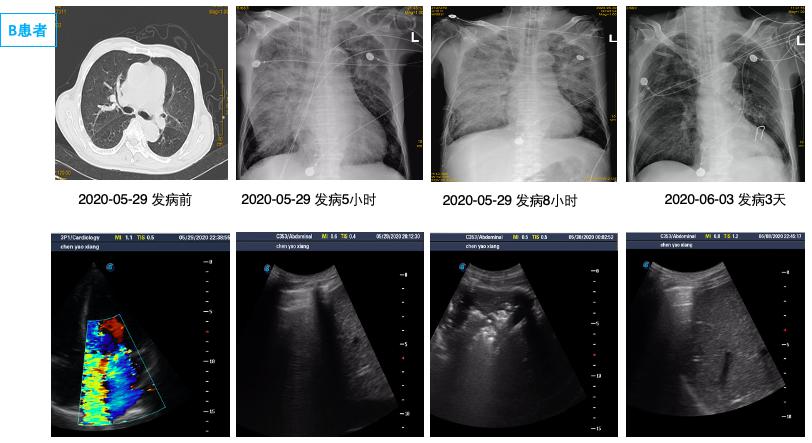

由于单侧PE病情轻重不一,影像表现可以为间质B线、毛玻璃影,严重可表现为肺实变,因此常误诊为肺部感染、肺出血、支气管扩张、肺实变等[29-31]导致病情延误。本研究中有12例单侧PE患者初次影像报告未准确识别; 因此建立重复可量化的单侧PE影像定义及分级标准有组于单侧PE诊断[32]。有心脏病史,心脏超声提示长期二尖瓣反流,长期有右侧胸腔积液,结合入院后床边BNP及肺部超声可以进行鉴别,尤其是床边重症超声可以及时发现明显二尖瓣反流,及时监测肺部超声表现可予以鉴别诊断。如图 4中B患者,入院前肺部CT正常,因失血性休克导致心脏骤停3 h后胸片提示右侧渗出加重,肺部超声由A线为主逐渐发展为B7线、B3线、融合B线及肺实变,提示患者PE程度逐渐加重; 同时心脏超声提示新发重度二尖瓣反流,综合考虑诊断单侧PE,经呼吸支持,利尿治疗后患者胸片、肺部超声均迅速恢复正常。而长期心衰合并二尖瓣反流患者,联合下腔静脉、颈静脉等超声进行容量评估,可与肺部感染相鉴别[33]。急性胸痛患者肌酸激酶同工酶联合床边及时检测肌钙蛋白,可早期诊断心肌梗死,为诊断心源性PE提供依据,本研究中两组间心肌损伤标志物差异无统计学意义。

| 图 3 单侧PE患者胸片及二尖瓣反流 Fig 3 X-ray and mitral regurgitation of Unilateral PE |

2 结果通过病历系统回顾性分析2018年1月至2021年1月,共纳入314例患者,其中男性179例,女性135例,年龄18~97岁[(58.8±16.9)岁]。单侧PE患者共14例,发病率4.5%,男性10例,女性4例; 其中以右侧为主单侧PE 11例(78.5%),左侧PE患者3例(21.5%)。1例单侧PE呈右肺上叶局限性分布,(见图患者C),1例单侧PE以左下肺为主(见图患者A),其余单侧PE分布无明显肺段特点。

在本次试验中单侧PE发生率为4.5%,高于国外心内科单侧PE 2.1%发病率[2]。同时本次14例单侧PE中,主要(11例,78.5%)为右侧PE,与国外研究类似(16例,89%)[2]。本研究中,两组间左心室射血分数、左心房前后径、左心室舒张末内径等心脏超声参数均差异无统计学意义,与既往研究类似。同时该研究发现单侧PE患者重度二尖瓣反流比例高达100%[2]; 提示二尖瓣反流是导致单侧PE的主要原因。本研究中重度二尖瓣反流在单侧PE组发生率显著高于双侧PE组,35.7% vs 14.0%,但显著低于前述研究,可能与患者纳入标准有关,有5例(35.7%)因心室颤动等原因导致心脏骤停。其中如图 2中D患者,女,32岁,眼眶下局麻后心脏骤停。心脏骤停后3 hCT提示左肺弥漫渗出,但复苏8 h后查心脏超声无明显二尖瓣反流,考虑与心脏骤停冠脉缺血导致暂时性二尖瓣反流有关[25-26],因此24 h后复查CT左肺单侧PE完全消失。